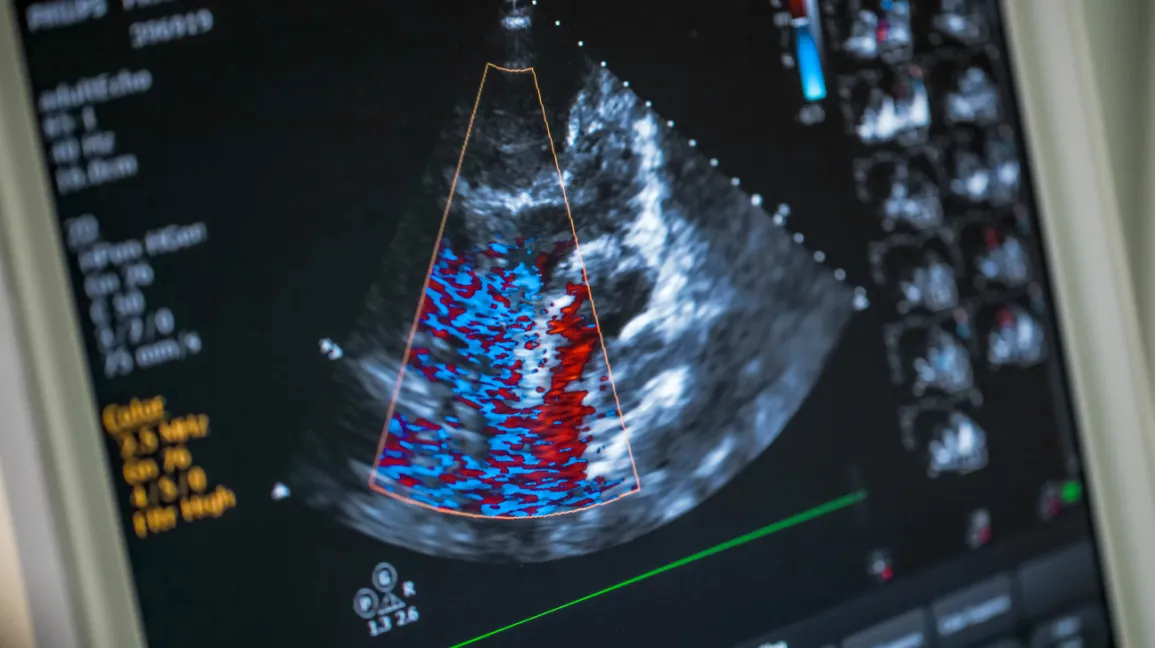

2-Dimensional Echocardiogram (Cardiac Ultrasound)

This is a safe and painless procedure that uses a transducer (a small, microphone-type device) to send high-frequency sound waves to the heart. The technologist can view the heart valves and pumping strength, look for structural defects, heart enlargement and/or fluid buildup. A Doppler exam and Color Flow exam are also performed. This allows doctors to evaluate blood flow through the heart. The technologist will videotape parts of the study for later diagnosis by the cardiologist.

Unlike sectional imaging technologies (CT and MRI) conventional echocardiography was unable to display neither spatial relationship to other structures nor multi-dimensional image representation. With the introduction of real-time 3D echocardiography, dimensional images of the heart, and especially of the heart valves, are now possible.